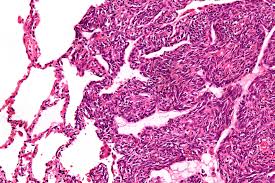

Synovial sarcoma is a rare and aggressive soft tissue sarcoma that most commonly arises near joints, tendons, or bursae, especially in the arms and legs. Despite the name, it does not originate from synovial cells. It affects young adults and adolescents, with a distinct chromosomal translocation

• Core needle biopsy for histopathology

• Immunohistochemistry and molecular testing (SS18-SSX fusion gene)